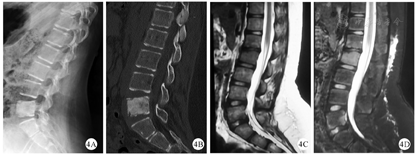

X线是临床上最常用的检查,通常X线在疾病初期无明显改变,随着疾病的进展,X线可显示早期溶骨性病变、硬化、骨扩张或后期呈混合性显像[20,21](图1)。在临床工作中,经验丰富的影像医生才能通过X线检查将CNO与骨肿瘤、感染性骨髓炎鉴别区分。对于无症状的CNO疾病,放射性核素骨显像是常用方法,但因其具有辐射,临床上广泛应用受到限制[22]。MRI是目前最具特异性的影像诊断方法,典型的MRI表现为初期的骨髓水肿,到后期的骨皮质变薄、溶骨性破坏伴硬化(图2、图3、图4)。全身MRI检查在急性炎症期最具有特异性,在MRI可以表现出T1序列低信号和T2序列高信号[21,23]。全身MRI检查在疾病的早期诊断中具有重要的意义,因为它能够在骨溶解、骨硬化之前检测到骨髓水肿和无症状骨病变,并且没有辐射,可用来监测随访骨骼病变的进展演变[24]。(图1、图2、图3、图4中影像学资料均来自同一患者)

多学科诊疗MDT在CNO疾病诊断、治疗过程中起着非常重要的作用。CNO患儿的初始症状多为骨痛,一般由小儿骨科或骨科医师首诊,在疾病的诊断过程中需要影像科、检验科、病理科、免疫风湿科、感染疾病科等众多学科的支持,确诊之后由免疫风湿科医师给予药物治疗,部分患儿需要外科医师进行骨活检以明确诊断。CNO累及脊柱椎体时需及时给予脊柱保护性支持、减少地面活动,避免产生脊柱侧凸、后凸畸形,当出现明显神经压迫症状后可行手术治疗。Hospach等[37]在大样本队列研究中发现约26%的CNO患儿存在脊柱病变,Pastore等[42]在研究中发现,累及脊柱的CNO患儿全部留下畸形或后遗症,建议重点关注。Baulot等[47]曾报道1例累及胸椎的CNO患儿,脊柱后凸逐渐加重,压迫椎管神经导致下肢无力、行走障碍,手术给予胸椎前路减压内固定术,术中用自体髂骨移植恢复椎体高度,术后12 d神经压迫症状完全消失,术后随访2年活动良好、神经压迫症状未复发,但留下了轻度的脊柱后凸畸形。